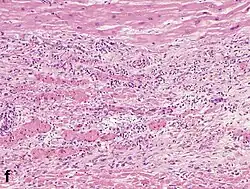

Under the microscope, myocardial infarction presents as a circumscribed area of ischemic, coagulative necrosis (cell death). On gross examination, the infarct is not identifiable within the first 12 hours.[20]

Although earlier changes can be discerned using electron microscopy, one of the earliest changes under a normal microscope are so-called wavy fibers.[21] Subsequently, the myocyte cytoplasm becomes more eosinophilic (pink) and the cells lose their transversal striations, with typical changes and eventually loss of the cell nucleus.[22] The interstitium at the margin of the infarcted area is initially infiltrated with neutrophils, then with lymphocytes and macrophages, who phagocytose ("eat") the myocyte debris. The necrotic area is surrounded and progressively invaded by granulation tissue, which will replace the infarct with a fibrous (collagenous) scar (which are typical steps in wound healing). The interstitial space (the space between cells outside of blood vessels) may be infiltrated with red blood cells.[20]

These features can be recognized in cases where the perfusion was not restored; reperfused infarcts can have other hallmarks, such as contraction band necrosis.[23]